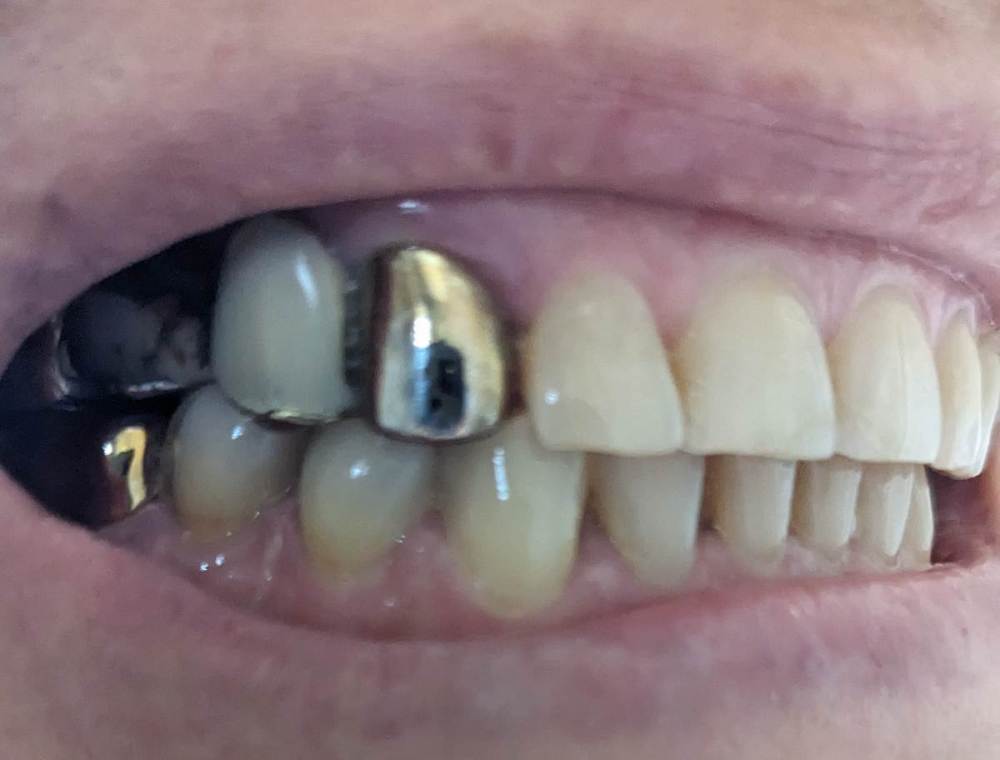

после сильного стресса нарушился прикус. на верхней челюсти боковые зубы сдвинулись вовнутрь, а передние ушли немного вперёд.

в детстве были полностью вырваны 4 и 5 зубы справа, и 6 слева. на боковых зубах справа и слева стоят рандолевые мосты - по четыре жевательных зуба (справа 3, 4, 5, 6 зубы. слева - 4 это отдельная коронка, а 5, 6, 7 - мост). хочу поменять эти мосты на металлокерамические. и есть желание выровнять кривой зуб (2 справа).

врач, который ставит коронки, говорит что новые мосты полностью исправят прикус, но есть сомнения, ведь передние зубы мосты не затронут.